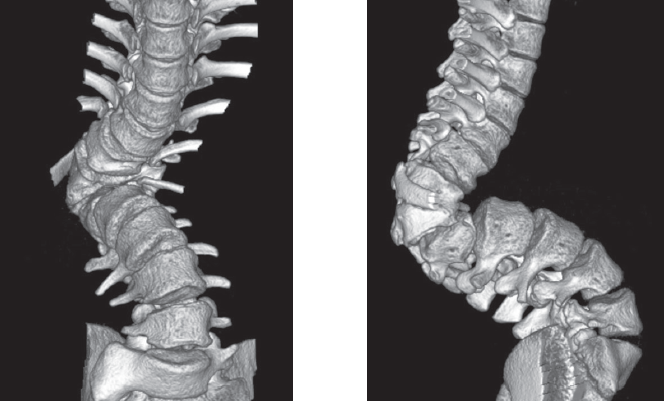

Неврологического дефицита нет (Frankel E). При магнитно-резонансной томографии данных за компрессионную миелопатию не получено. При компьютерной томографии (рис. 1) определить природу порока развития затруднительно в связи с выраженными вторичными изменениями смежных сегментов. Для анализа представлены рентгенограммы, выполненные в раннем возрасте (5 месяцев, 1 год 7 месяцев; рис. 2, 3).

Рис. 2. Рентгенограммы в возрасте 5 месяцев

Рис. 3. Рентгенограммы в возрасте 1 год 7 месяцев